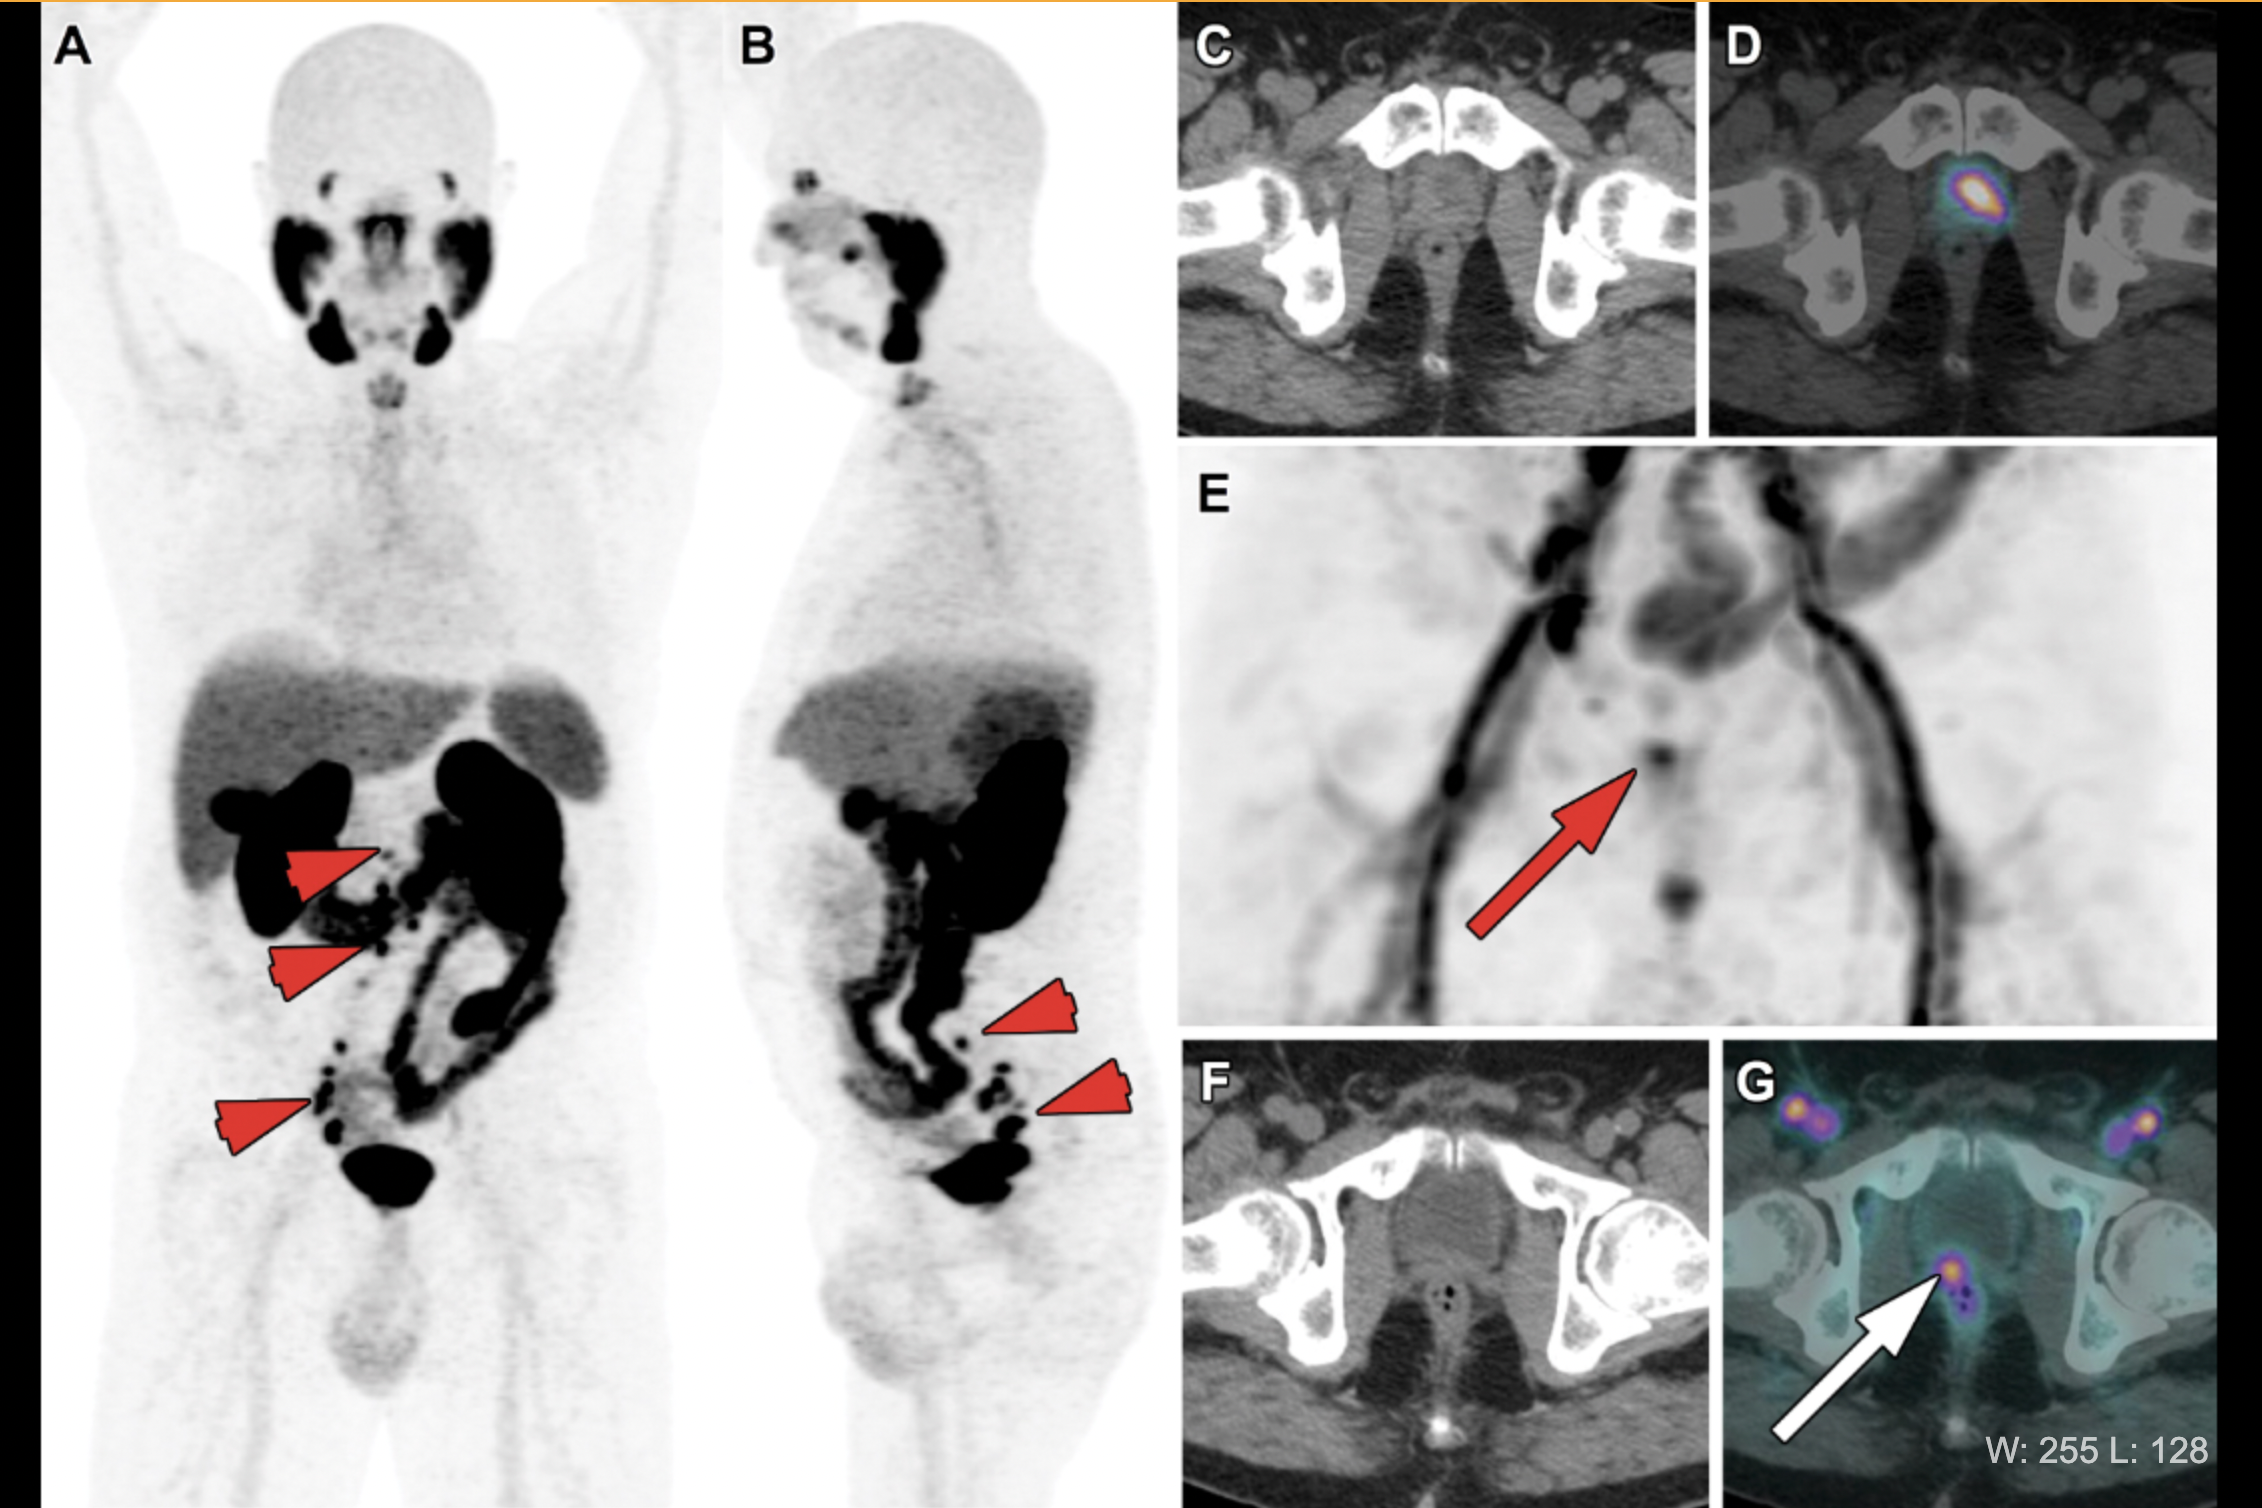

Cancers, Free Full-Text

The prognostic value of lymph node staging with prostate‐specific

Frontiers Incorporating PSMA-Targeting Theranostics Into

Diagnostics, Free Full-Text

Diagnostics, Free Full-Text